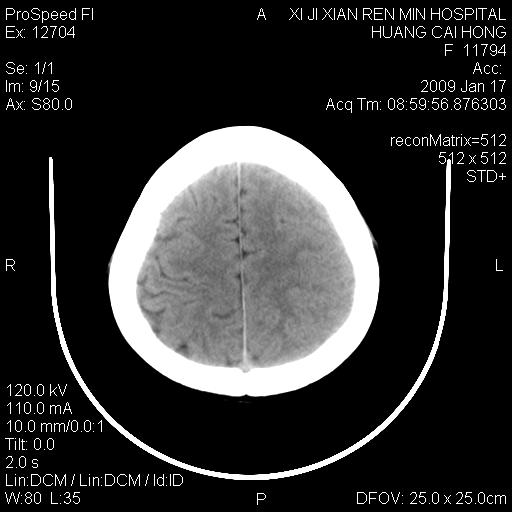

以下是引用zbp537在2009-1-19 13:54:00的发言:[br]首先考虑脑炎。[br]诊断依据:[br]1、患者较年轻。[br]2、有感冒病史。[br]3、左侧颞枕叶这么大一片低密度影,占位征象却不明显,不符合肿瘤特征,其内的高密度影为出血灶。

以下是引用xiaoniu在2009-1-19 13:29:00的发言:[br]左侧颞叶三角形低密度影,占位效应不明显,其内点片样高密都影,青少年患者,首先考虑:少突胶质瘤。因为有感冒病史,不能除外感染的可能。